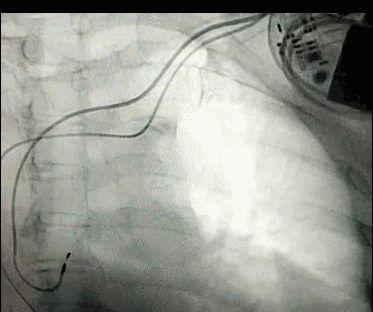

DSA是將造影劑注入需要檢查的血管中,使血管顯露原形,然后通過系統(tǒng)處理,使血管顯示更加清晰,便于醫(yī)生診斷或進行手術(shù)。

數(shù)字減影血管造影術(shù)是醫(yī)學(xué)影象學(xué)中,繼X線CT之后的又一項新技術(shù),也是當(dāng)前醫(yī)學(xué)影象學(xué)中具有突破性的重大進展。?